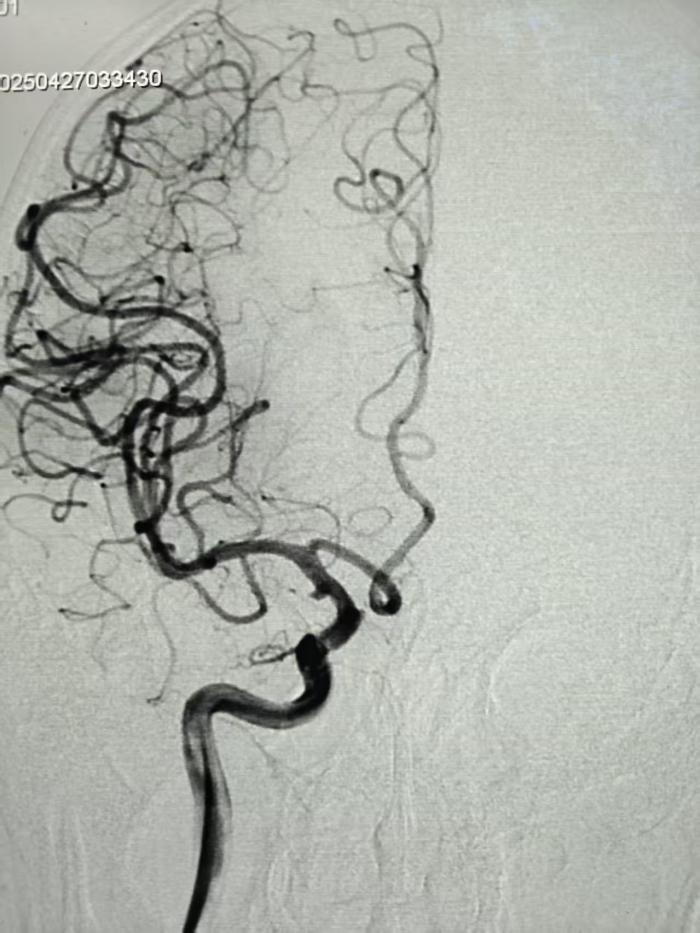

步步惊心:三维路图引导下的“双线作战”

凌晨3:05,静脉溶栓药物注入患者体内,介入团队同步开展术前准备。面对血管严重迂曲,手术团队采用“长鞘+支撑导管+支架导管同轴技术”,利用三维血管路图精确定位。术中可见取栓支架释放后,血栓与动脉瘤相距不到2cm,主刀医生康敬源巧妙调整导管角度,以“悬空穿越”方式避开动脉瘤体,最终采取SWIM技术一次性取出多块混合型血栓,最大者4mm*2mm。

凌晨4:24,黄老先生原本闭塞的血管,顺利实现三级再通,动脉瘤完好无损。从接诊患者到完成手术,全程只用了79分钟。